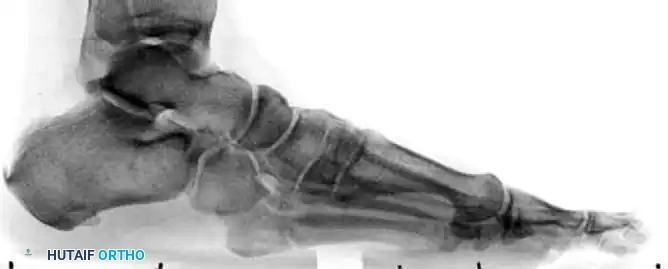

PREOPERATIVE PLANNING AND IMAGING

Standard weight-bearing anteroposterior (AP), lateral, and oblique radiographs of the foot are mandatory. The oblique view is particularly useful for profiling the fracture line at the metaphyseal-diaphyseal junction.

In cases of delayed union or nonunion, advanced imaging such as a Computed Tomography (CT) scan may be warranted to assess the extent of medullary sclerosis and to precisely measure the canal diameter. The medullary canal of the fifth metatarsal is not perfectly straight; it exhibits a lateral and plantar bow. Preoperative templating is critical to select a screw diameter that achieves cortical purchase without causing iatrogenic lateral cortical blowout.

The patient is placed in the lateral decubitus position, or supine with a large bump under the ipsilateral hip to internally rotate the leg, bringing the lateral border of the foot directly toward the ceiling. A radiolucent table is mandatory to allow unobstructed fluoroscopic imaging in multiple planes. A thigh or calf tourniquet is applied.

- Guidewire Insertion: Use a stout guide wire (typically 1.4mm or 1.6mm) to find the medullary canal. This can be technically demanding. The wire must lie almost parallel to the hindfoot and the plantar aspect of the foot.

- Fluoroscopic Confirmation: Advance the wire under multi-planar fluoroscopy. Ensure the wire passes the fracture site and sits centrally within the narrowest portion of the diaphysis (the isthmus).